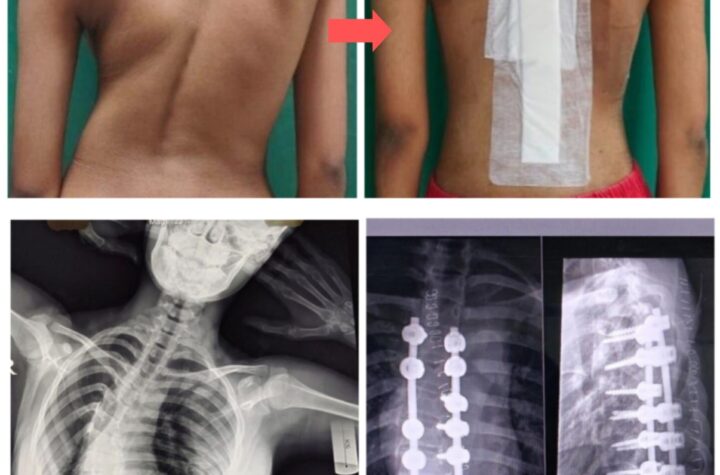

भोपाल: 3 मई 2025 एम्स भोपाल के कार्यपालक निदेशक प्रो. (डॉ.) अजय सिंह के मार्गदर्शन में, संस्थान निरंतर चिकित्सा सेवाओं...